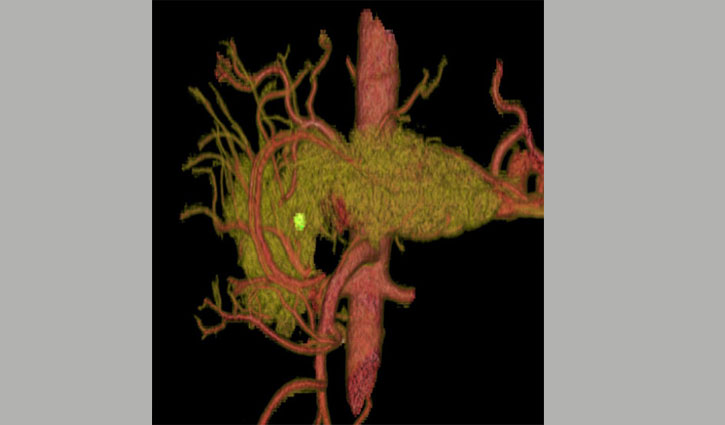

ত্রিমাত্রিক কম্পিউটেড টমোগ্রাফি (সিটি) স্ক্যানের ছবিটি একটি অগ্নাশয়ের। এখানে সবুজ অংশটি অগ্ন্যাশয়ের ক্যানসার টিউমার। রোগীদের মাত্র পাঁচ শতাংশ এই রোগে টিকে থাকতে পারে।